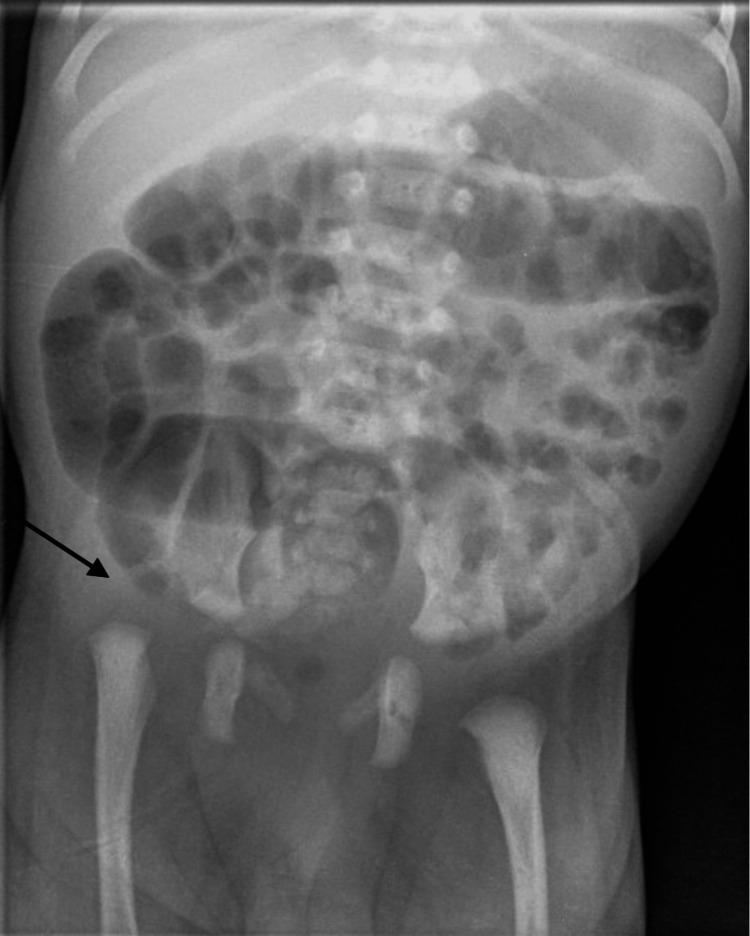

Pseudoaneurysm following percutaneous tendoachilles (TA) tenotomy is a rare complication found in children with congenital talipes equinovarus (CTEV). It is postulated that associated aberrant vascular anatomy in combination with CTEV may be the underlying aetiology. In this case report, we describe a case of a toddler who developed bilateral pseudoaneurysms following percutaneous tendoachilles tenotomy and explore the management and outcome in relation to this. Based on this case report and a review of the literature, the consistent clinical findings of swelling and/or discolouration due to pseudoaneurysm occur at three weeks post-tenotomy, and should raise suspicion for the diagnosis. Furthermore to the best of our knowledge, this is the first case report of bilateral pseudoaneurysms in the same setting, and we propose the possibility of an aberrant vessel arising from the peroneal artery that may be prone to injury.

经皮跟腱切断术后假性动脉瘤是先天性马蹄内翻足(CTEV)患儿中罕见的并发症。据推测,CTEV合并异常血管解剖结构可能是其潜在病因。在本病例报告中,我们描述了一名幼儿经皮跟腱切断术后出现双侧假性动脉瘤的病例,并探讨了相关的治疗方法及结果。基于本病例报告及文献回顾,假性动脉瘤导致的肿胀和/或变色等一致的临床症状出现在跟腱切断术后三周,应引起对该诊断的怀疑。此外,据我们所知,这是同一病例中双侧假性动脉瘤的首例病例报告,我们提出可能存在一条来自腓动脉的异常血管,该血管可能易于受伤。